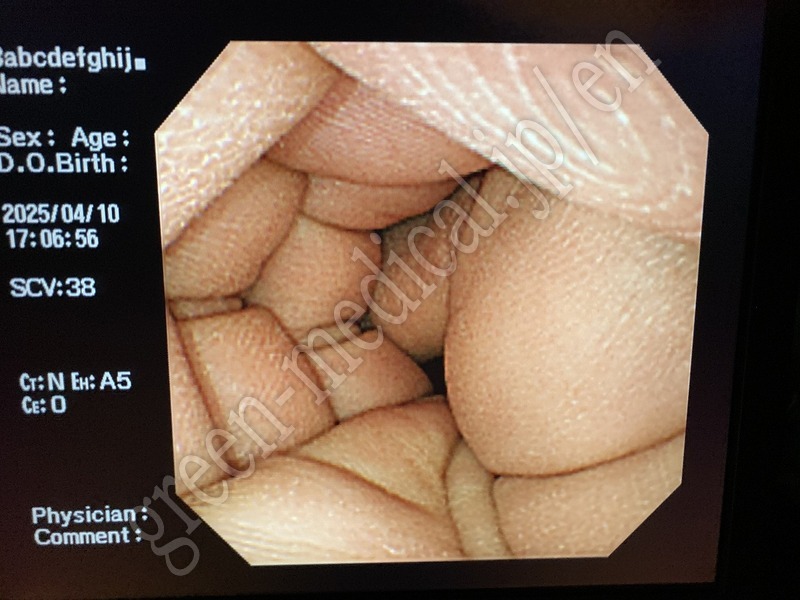

Video Transnasal Gastroscope .GIF-XP260NS

OLYMPUS

.GIF-XP260NS